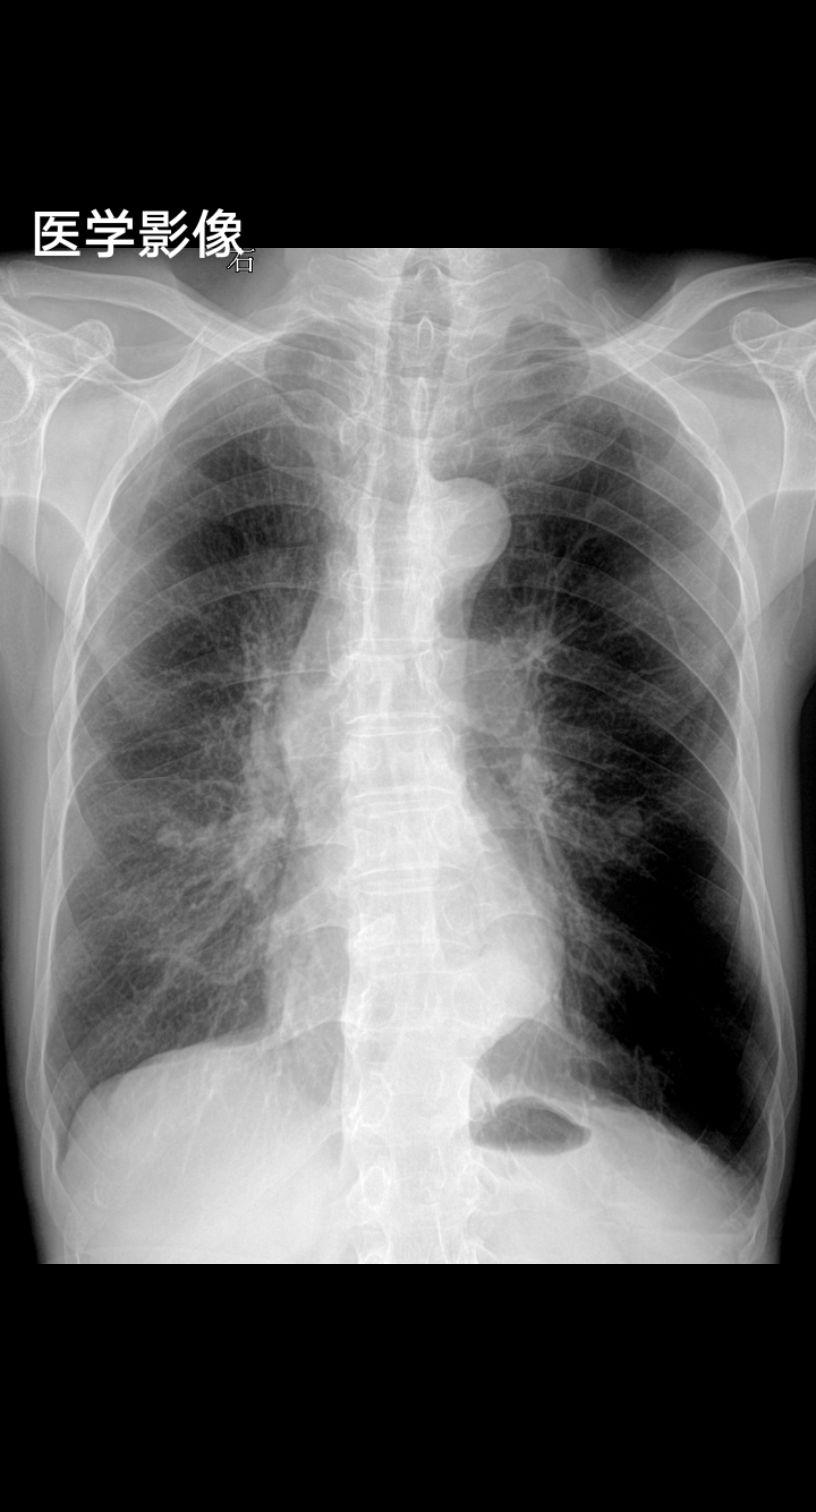

家人们你们拍胸片的时候让患者深呼吸憋气吗 患者主诉咳嗽感冒一周29岁女